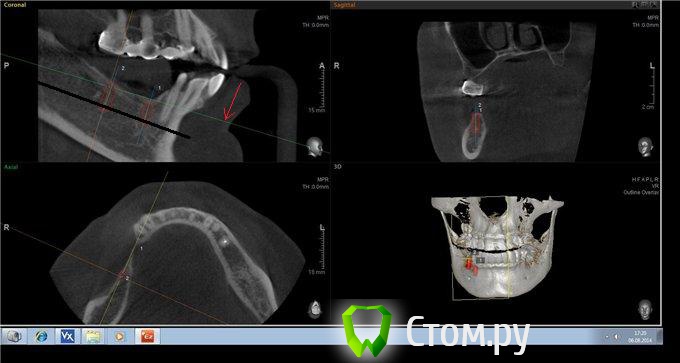

Аслан Опубликовано 6 августа, 2014 Поделиться Опубликовано 6 августа, 2014 По финансовым соображениям все поэтапно раздельно.Есть пациентка с деффектом в 4ом сегментеhttp://s014.radikal.ru/i328/1408/31/7b904e0bd16at.jpg Изначально поанировал так1)разрез, отслойка, мобилизация лрскута, забор ауто, замес с апатос.2) ламина вестибулярно винтами, в середине провала вертикального "каркасные" винты 2штуки, засыпать графтом, уплотнить, завернуть ламину, подшить3) все ушить. Пластика мягких тканей по ситуации либо сразу, либо потом. Второй вариантВместо ламины использовать эволюшн и фиксоровать ее пинами вестибулярно внизу 3, язычно 2. Вот все замеры.http://s017.radikal.ru/i426/1408/cf/548eb9ec2bf5t.jpghttp://i068.radikal.ru/1408/1a/444c9534b91et.jpg Ссылка на комментарий

Аслан Опубликовано 6 августа, 2014 Автор Поделиться Опубликовано 6 августа, 2014 (изменено) Можно обойтись без вертикальной аугментации в этом отделе, по высоте вроде нормально.Сделай расстановку имплантатовУже делал. 8кой можно впринципе и обойтись без большой вертикалки, до канала там 10 мм от вершины гребня. Но учитывая, что имплант надо погружать, то там "впритык". Надя,Технически это нечем пока. Изменено 6 августа, 2014 пользователем Аслан Ссылка на комментарий

kriokov Опубликовано 6 августа, 2014 Поделиться Опубликовано 6 августа, 2014 Аслан, если не трудно залейте кроссекции в позиции 46 и 47.и канал если можно не отмечайте маркером. Ссылка на комментарий

Аслан Опубликовано 6 августа, 2014 Автор Поделиться Опубликовано 6 августа, 2014 По попядку 45 46 47http://s017.radikal.ru/i421/1408/11/dfe815093cc7t.jpghttp://s003.radikal.ru/i204/1408/07/b726807c431bt.jpghttp://s019.radikal.ru/i637/1408/1c/da96558b4755t.jpg 45 имплант 3610http://i056.radikal.ru/1408/f1/dd0b552fa46ct.jpg47 - 3810http://i074.radikal.ru/1408/17/6372dd9a8092t.jpg Ссылка на комментарий

kriokov Опубликовано 6 августа, 2014 Поделиться Опубликовано 6 августа, 2014 Аслан, ось показанную стрелкой лучше на уровне канала выставлять или верхушек зубов если есть по соседству. Согласен с Антоном, нкр пройдет Ссылка на комментарий